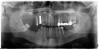

neuda4nik Опубликовано 31 мая, 2012 Поделиться Опубликовано 31 мая, 2012 (изменено) Здравствуйте уважаемые доктора! История началась давно, ещё в советские времена, когда лечение зуба закончилось потерей сознания и как следствие я у докторов не показывался лет 15.... В 2008 прижало так, что откладывать дальше было нельзя и я отправился к стоматологам. Что-то полечили, ещё больше удалили, вкрутили штифтов и даже водрузилимост. Современные доктора оказались не в пример человечнее советских и я практически восстановил веру в "Добрых Стоматологов" . После всех этих процедурвстал резонный вопрос: "Что делать? Кто виноват?? Где водка???" Что делать с освободившимся после удаления порушенных зубов местом?Вариант собственно просматривался один - имплантация. Доктор сказал, что это исскуство ему знакомо и можно буквально в ближайшие дни приступать.В то время в нашем 500тыс городишке импланты ставили в трёх-четырёх клиниках, так что выбора практически и не было. В общем первый имплант, верхняя 4 справа прижился на "Ура" (кстати по внешнему виду можно предположить, что это за система?) и планы были радужные - в течение2009 года поставить ещё 6 имплантов и закончить протезирование. К сожалению дальше планов дело не пошло Второй имплат, установленный на место правой нижней 6 просидел в челюсти пару недель и был удалён после того, какя съел 4 коробки кеторола и практически не мог спать и работать. Температура, озноб, непрекращающаяся боль в месте установки - полный "фарш" в общем. Во времядеимплантации из под импланта буквально ударил фонтан гноя, доктор удивился и сказал, что это в его практике первый случай. Буквально через сутки здоровьенормализовалось и я на 3 месяца отправился отдыхать. На локальной картинке с визиографа было видно, что имплант зацепил лунку соседнего зуба. Ну по крайней меремне так показалось. Доктор сказал, что это просто наложение проекций, а имплант и соседний зуб по факту в разных плоскостях стояли. Через 3 месяца была предпринята ещё одна попытка поставить имплант на это же место. Всё прошло достаточно мирно и ничего сильно не болело, но при осмотре доктор был не рад.Имплант не прижился. Подождав пару месяцев и так и не дождавшись положительного результата имплант был удалён. На этот раз "отдых" от стоматологов продлился почти 3 года.Периодически встречая доктора узнал, что он поменял систему и в клинике стоит новое оборудование.В январе 2012 я пошел на 4 заход! Имплант системы Superline, был снова установлен на то же самое место, и нормально прижился! Тут же по горячим следам была поставленанижняя правая Superline семёрка и она тоже "прикипела"! Я поспрял духом и на горизонте замаячило зубастое щастье, но не тут то было!Следующими на очереди планировались верхняя правая 6 и 7 от Superline одномоментно, на фото вы можете наблюдать две "зияющие пробоины" на этом месте. Операцияпрошла вполне мирно и особо не болело, но через пару недель я обнаружил, что что-то в десне качается. К сожалению десна не срослась полностью и в маленькое "окно" былавидна заглушка импланта. Мне показалось, что это заглушка выкрутилась и болтается в импланте. Каково же было моё удивление, когда пошевелив языком я "выудил" из "окна"весь имплант целиком Вот так без объявления войны имплант записался в дисиденты и свалил из челюсти."Семёрочка пошла!" Отнёс его в пакетике к доктору, который недоумевал не меньше моего. Я настойчиво спрашивал у доктора - не нужно ли принимать какие-то специальные препараты для лучшего "прикипания" импланта к десне. Доктор сказал, что всё должнопроисходить естественным путём и никакой химией пользоваться не нужно. На носу был трекинг в Гималаях (Kanchenjunga) и мы решили с доктором встетится по приезду из отпуска, в конце мая.26 числа я пришел в клинику с целью открыть "шестёрку", установить формирователь и определиться с дальнейшими планами.Накануне я потрогал "шестёрку" пальцами и мне показалось, что она качается. Ну.... в общем она тоже записалась в дисиденты и свалила от меня. Я как-то совсем расстроился, и в таком расстроенном состоянии предложил доктору раз уж я пришел в клинику, завернуть пару саморезов в левый низ на место 6 и 7,если конечно нет никаких противопоказаний к этому. Доктор сказал, что противопоказаний нет и за час вкрутил мне пару имплантов, сразу установив в них формирователи.Сказал, что это нормальная практика для нижней челюсти. На фото видно, что на этот раз импланты поменьше диаметром, чем с другой стороны.Про систему я не спросил, но в сл. вторник на осмотре спрошу. Я просил вкрутить такие же как прижились с другой стороны. Сутки организм ничего не замечал - вообще не было даже намёка на какую-то боль!Через сутки заболело, поднялась температура 37.3. Всё было прибито кеторолом и анальгином. Но боль возвращалась и пришлось слегка кеторолить её.После этого я решил поискать в инете, что пишут насчёт улучшения приживаемости. Вот так я и набрёл на этот сайт.Тут я вычитал, что практически все пьют антибиотики после установки имплантов - Амоксиклав. Позвонил доктору, он сказал, что назначает, но в крайних случаях.Посчитав свой случай крайне крайним (ну сколько уже можно-то!!!) я спросил доктора насчёт курса антибиотика - он не возражал. Я немедленно отправился в аптеку.А теперь собственно картинка зубов. Сам сегодня пошел и сделал панораму прочитав правила форума. Разруха конечно зачётная, но есть желание довести дело до победы! Что скажите уважаемые?Читаю о 99% приживаемости, как о каком-то чуде. У меня из 7 прижилось только 3 Два, которые вкрутили 26 мая, ещё "чужие среди своих". Побаливают чуток, но терпимо.Что не так? Доктор что-то неправильно делает или я такой? Может фаза Луны не та, или ещё какая мистика?Что предпринять сейчас?Прошу извинить за столь длинный рассказ. Линки на картинки в большем разрешении.http://dl.dropbox.co...mp/P5311265.jpghttp://dl.dropbox.co...mp/P5311264.jpg Изменено 31 мая, 2012 пользователем neuda4nik Ссылка на комментарий

neuda4nik Опубликовано 4 июня, 2012 Автор Поделиться Опубликовано 4 июня, 2012 Добрый день. Удалось сбросить карточки на диск.Удивлён такому низкому разрешению исходников.Наверное установка древняя стоит с маленькой матрицей.Первая карточка сделана 27/01/2012, вторая 31/05/201236 и 37 помаленьку приживаются, уже практически не беспокоят. Сейчас видимо пару месяцев надо отдохнуть для восстановления кости на месте 16 и 17и снова пробовать крутить туда имплантаты? Ссылка на комментарий

neuda4nik Опубликовано 6 августа, 2012 Автор Поделиться Опубликовано 6 августа, 2012 Здравствуйте!Утром поставили 16 и 17На место 16 установили 11.5х3.5, а на 17 поставили 10.0х5.015 оставили жить на данном этапе.Доктор уплотнял кость - колотил молотком минут 10 наверное. Положили костный материал сверху, прикрыли мембраной, ушили, прописали Амоксиклав, Линекс и отправили домой Завтра с утра осмотр. Вот что имеем на данный момент - однако хороший зоопарк собрался http://db.tt/ld3t6IuQ 16 судя по картинке поставили в перегородку между 16 и 17 - там кости больше было.у него теперь будет номер 16.5 Доктор ручкой на картинке нарисовал предполагаемое расположение коронок. Если бы на месте 16 оказалось мало кости, имелся запасной вариант с удалением 15 и установкоймоста 15-17.5, но обделались малой кровью Имплантаты израильские - Hi-Tec НМВ всё прошло не плохо. Несколько удивило обезболивание.После укола доктор стал делать операцию буквально через 2мин.Никакой чувствительности не было - как обухом по голове.И отпустило очень быстро и резко часа через 1.5 - еле успел до кеторола добежать. Ссылка на комментарий